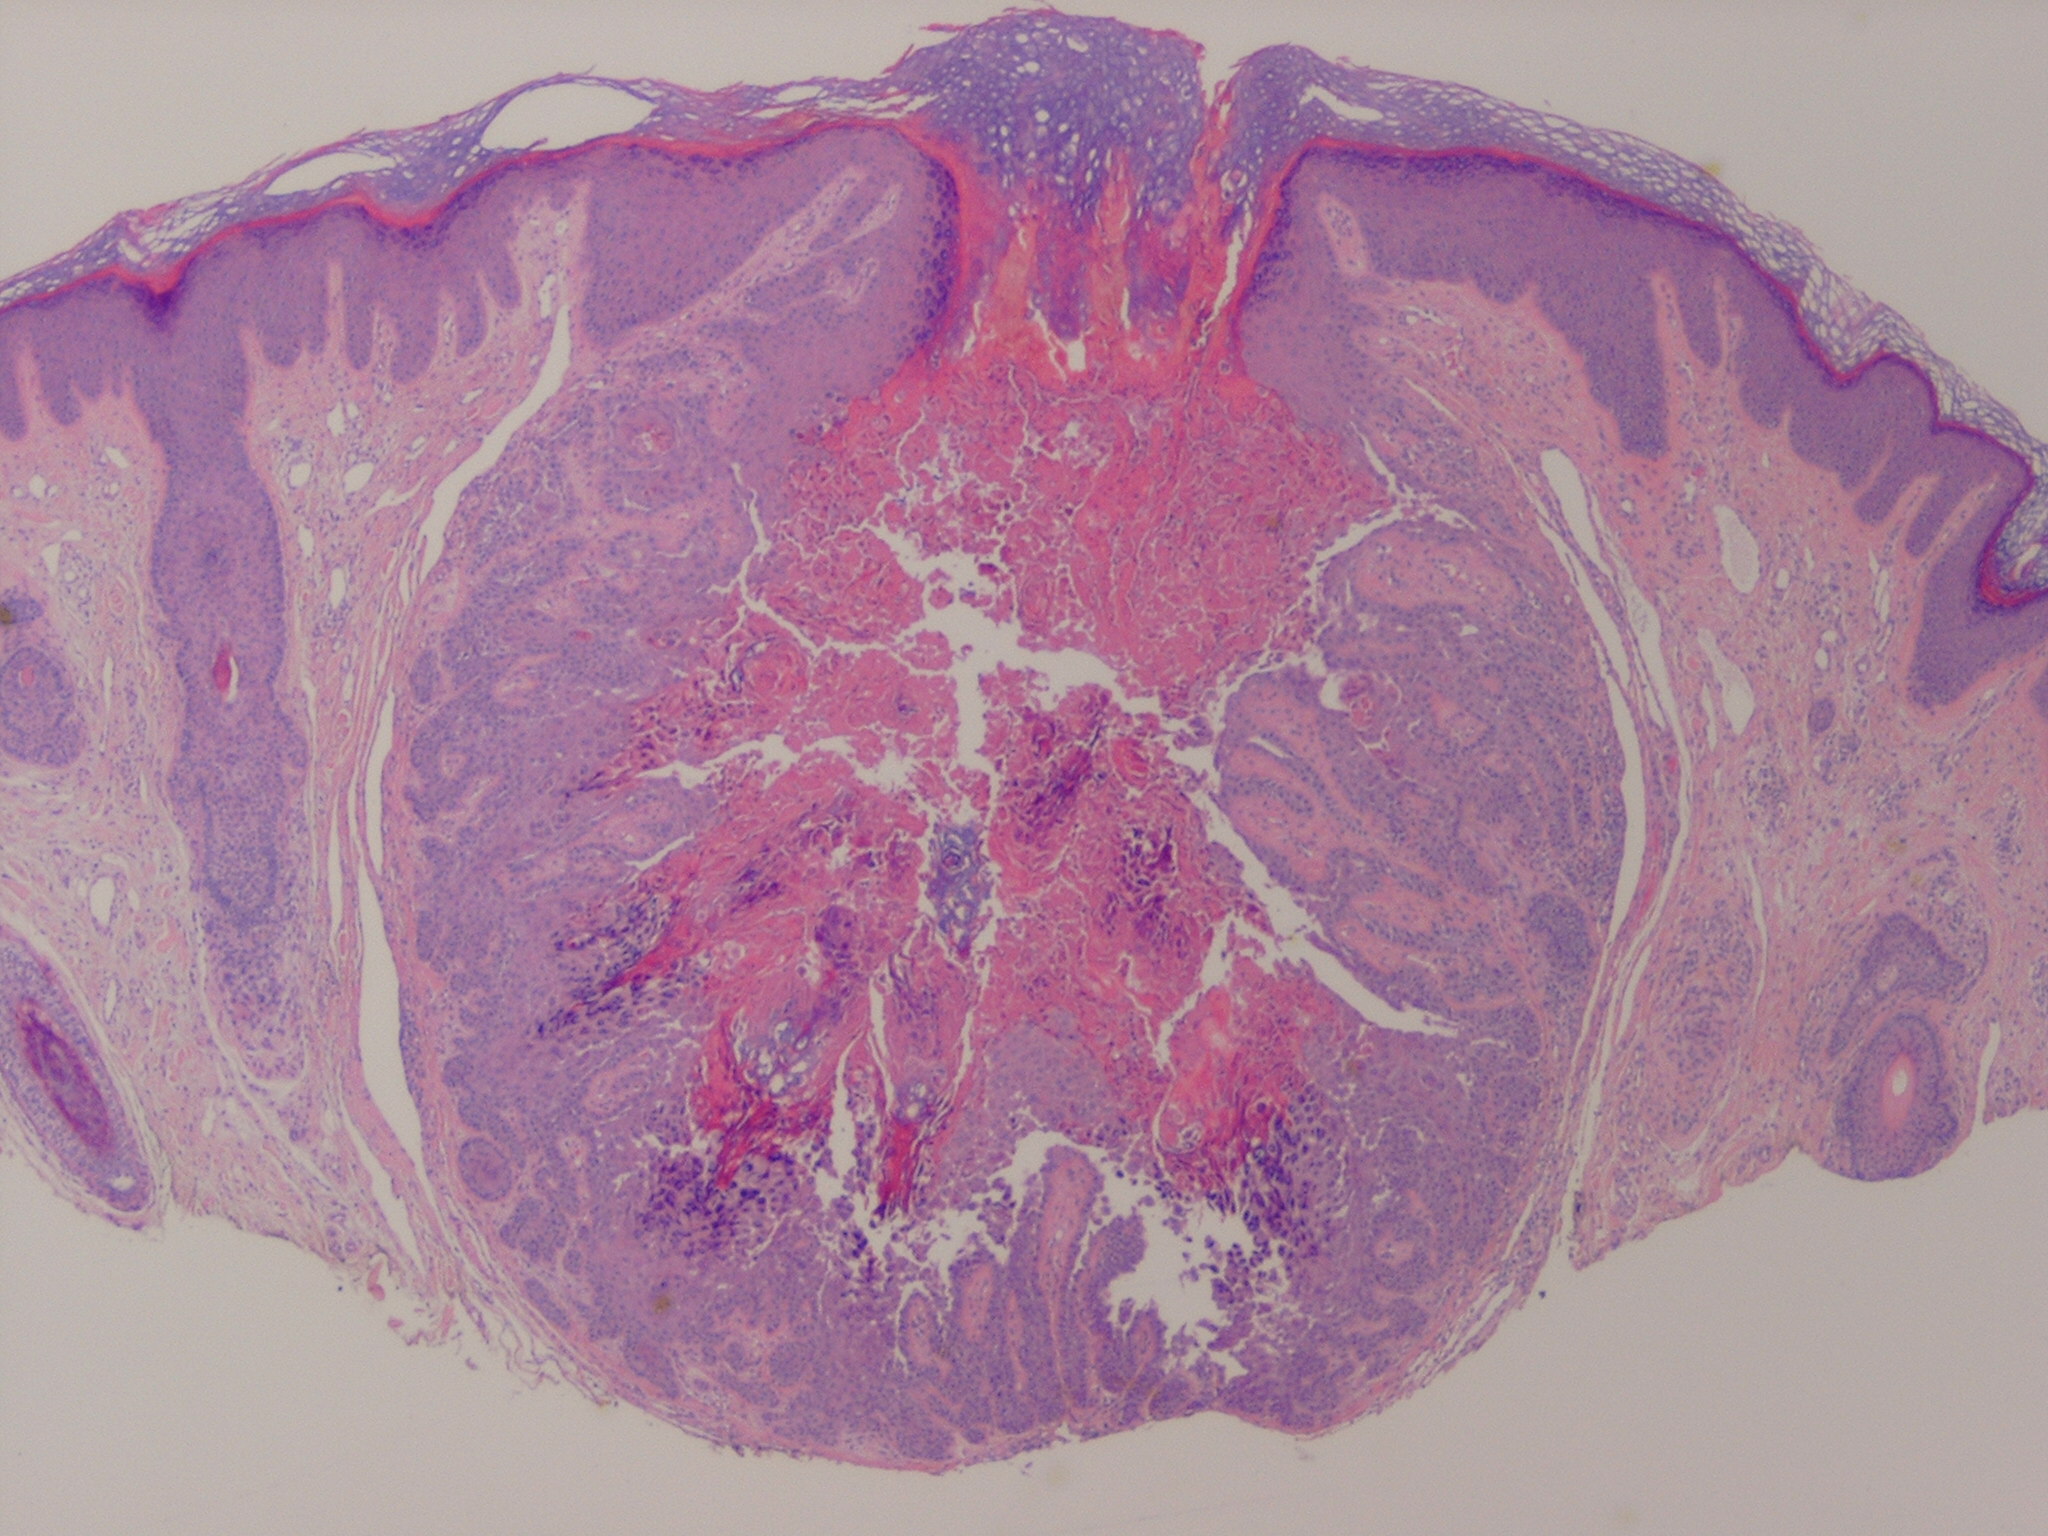

Histopathology.

The center of the lesion is occupied by a large, cup-shaped invagination connected with the surface by a channel filled with keratinous material . The large invagination contains numerous acantholytic, dyskeratotic cells in its upper portion. The lower portion of the invagination is occupied by numerous villi, that is, markedly elongated dermal papillae that are often lined with only a single layer of basal cells and project upward from the base of the cup-shaped invagination  . Typical corps ronds can I

usually be seen in the thickened granular layer lining the channel at the entrance to the invagination .